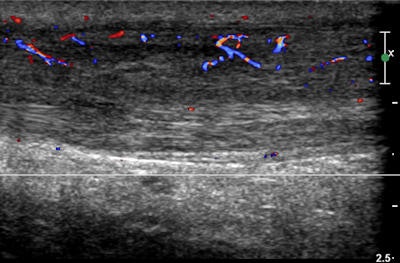

Ultrasound shows thickening of the left Achilles tendon in a 34-year-old man who is a triathlete. Neovascularity is in keeping with Achilles tendonitis. Image courtesy of Dr. Denis Remedios.

Ultrasound shows thickening of the left Achilles tendon in a 34-year-old man who is a triathlete. Neovascularity is in keeping with Achilles tendonitis. Image courtesy of Dr. Denis Remedios.The aim of the study was to determine the ability of ultrasound-guided intervention to reduce recovery time and return to field of play. Patients were divided into groups composing those who received ultrasound scans without further intervention, and those who received ultrasound scan with intervention, such as steroid injection therapy or paratenon stripping. Time to return to sport, types of injuries, and outcomes in terms of medals won were the primary study endpoints.